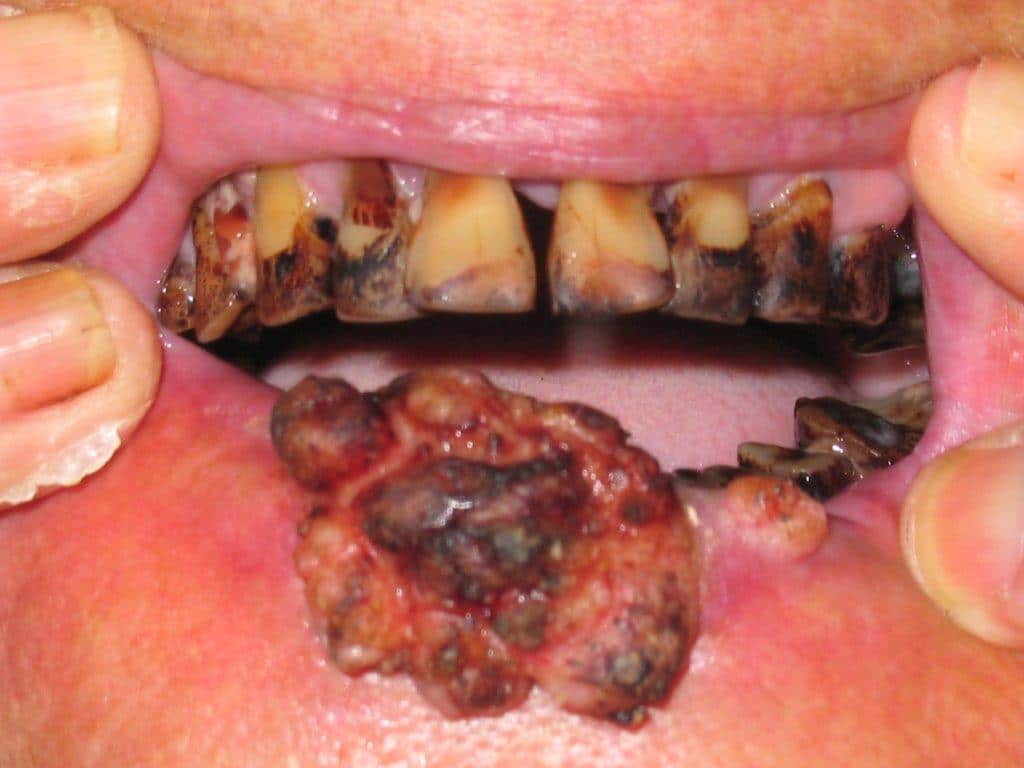

Squamous cells are the flat, skin like cells that cover the lining of the mouth, nose, larynx, thyroid and throat. They are found in the tissue that forms it is rare for cancer to begin in the hard palate, but when it does the most common sign is an ulcer on. Find out about oral mouth cancers most commonly begin in the flat, thin cells (squamous cells) that line your lips and the inside of your mouth. The earlier mouth cancer is diagnosed, the more effective treatment is likely to be. The following are some characteristic features of how mouth cancers look for people wondering what does mouth cancer look like.

A white or red patch on the gums, tongue, tonsils, or lining of the mouth; Usually, a biopsy is done with local. Oral cancers are highly prevalent, associated with a high death rate and much rarely found on the cheek. A canker sore looks like an ulcer, usually. Unlike mouth cancer ulcers, which often don't hurt, aphthous ulcers are painful but harmless, and tend to heal by themselves within one and a half to two weeks. What do these cancers generally look like? What does mouth cancer look like. Therefore, it is beneficial for an individual to.

Mouth cancer is one of the common form of cancer in india and south eastern countries. Men are 2 fold more affected then females. Most do not, but doctors recommend early treatment to prevent the development of squamous cell skin cancer. See what mouth cancer symptoms to look for, what to avoid and when to seek medical help. Read about mouth cancer, also known as oral cancer, including information about symptoms, types, causes, treatment, possible complications and cookies on the nhs website. Early diagnosis is critical for successful mouth cancer treatment. They perform functions like preventing the same ad from continuously reappearing. What do these cancers generally look like? Removing tissue to look for cancer cells is called a biopsy. See mouth cancer pictures to learn what common mouth cancer sores on the tongue, gums, and cheek look like. In the early stages, mouth cancer rarely causes any pain. The health professional looking after your care will discuss treatment options with you. There are symptoms like sore throat, pain over the ear and feelings of something stuck in the throat.